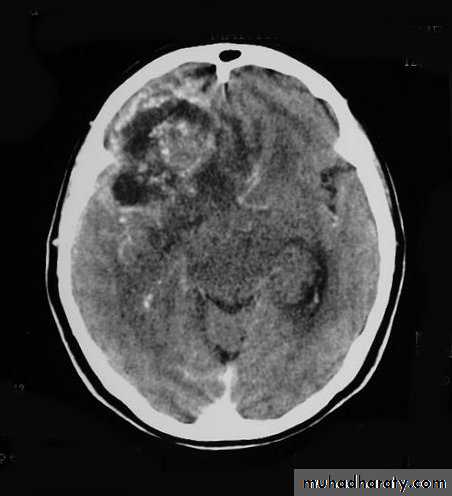

Metastatic Brain Tumours

Metastatic Brain Tumours Post contrast CT